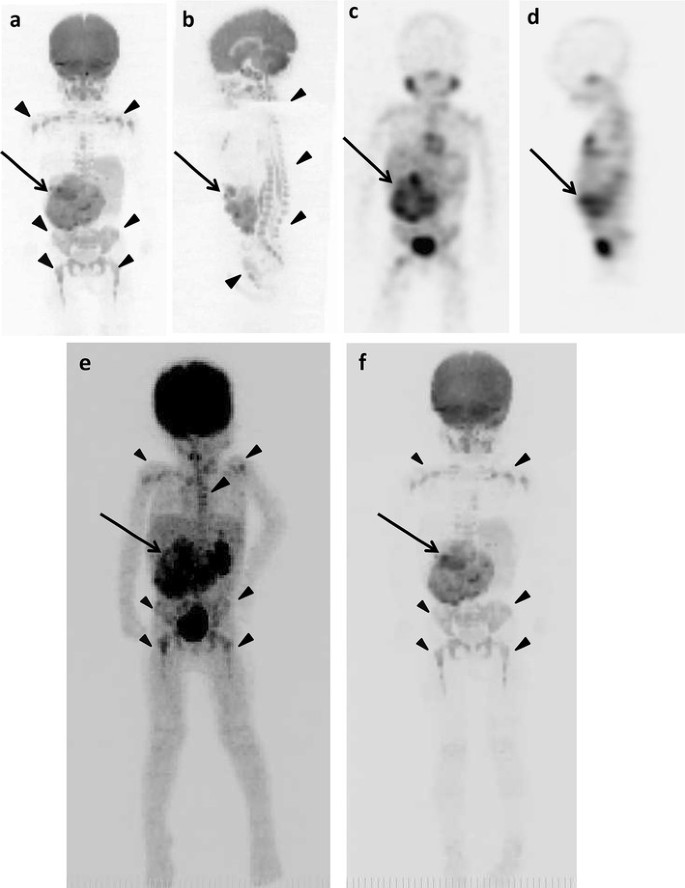

The example false-positive images in various bone segments by DWIBS are shown along with the negative results by 18F-FDG PET/CT, 123I-MIBG scintigraphy/SPECT-CT, and bone scintigraphy/SPECT in Figs. 1, 2, 4, 5 and 6. Diffuse intensive false-positive signals by DWIBS are seen in pelvic bones (iliac and sacral bones) (Fig. 4a). Faint diffuse false-positive signals are seen in various bones (Figs. 5, 6).

Fig. 5

figure 5

The original lesions in right adrenal gland and false-positive images in various bone segments of 2 years and 9 months old girl (patient 1). a DWIBS (anterior). b DWIBS (lateral). c 123I-MIBG scintigraphy/SPECT (anterior). d 123I-MIBG scintigraphy/SPECT (lateral). The MIP of 18F-FDG PET (e) and DWIBS (f). Long arrows show the original lesion (af). Arrowheads show false-positive images (a, b, e, f)

Fig. 6

figure 6

The original lesion in left adrenal gland and false-positive findings in various bone segments of 2 years and 8 months old boy (patient 10). a DWIBS (anterior). b 123I-MIBG scintigraphy/SPECT (anterior). The MIP of 18F-FDG PET (c) and DWIBS (d). Long arrows show the original lesion (ad). Arrowheads show false-positive images (a, c, d)

In the present study, false-positive findings at whole-body DWIBS were seen in all bone segments (Table 8). Typical patterns of signal distribution in false-positive findings were high diffuse signal in pelvic skeleton and faint diffuse signal in the other bone segments (Figs. 4, 5, 6). All the 13 pediatric patients studied in the present study were younger than 5 years of age. Patterns of false-positive findings in pelvis at DWIBS were very similar to high signals in pelvis of healthy children reported by Müller et al. [26], whereas faint diffuse signals as false-positive findings in lumbar spine seen in the present study were different from typical patterns found in lumbar spine of healthy children reported by them [26]. True reason for the differences in the patterns of false-positive signals at DWIBS in lumbar spine between our findings and those reported by them is unknown. However, the results of the present study provide the same conclusion as theirs that DWIBS should be carefully used for cancer staging in children because of its high incidence of false-positive findings in skeletons.